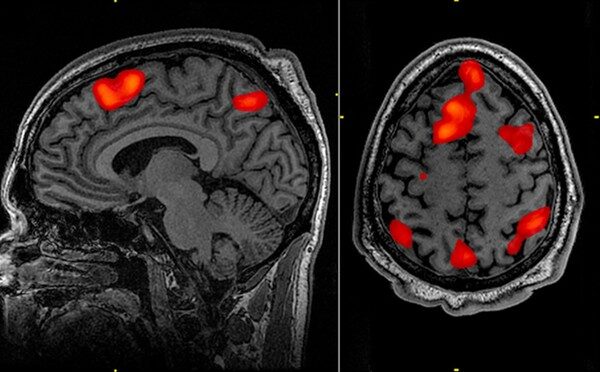

É citada como fonte da declaração da professora Sarah Tabrizi e como provedora de uma ilustração gráfica. Sua menção é puramente referencial.